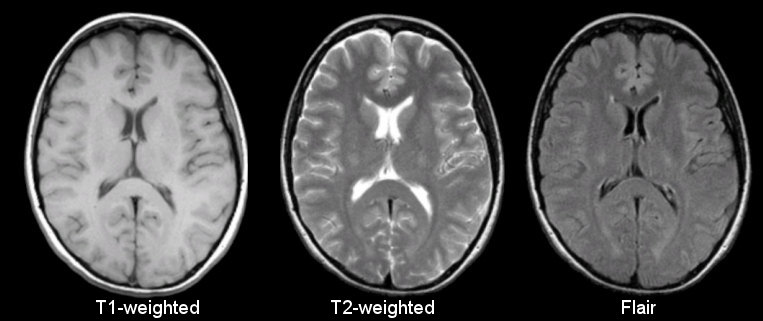

Structural MRI

MRI Physicist develops sequences